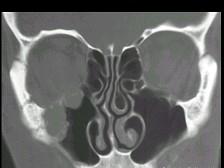

问题 女性,50岁,右鼻塞、脓涕3个月,CT、MRI检查如图所示,请选择正确的答案 ( )

选项 A、右侧上颌窦黏液腺瘤 B、右侧上颌窦腺样囊性癌 C、右侧上颌窦粘膜下囊肿 D、右侧上颌窦积液 E、右侧上颌窦黏液囊肿

答案 B